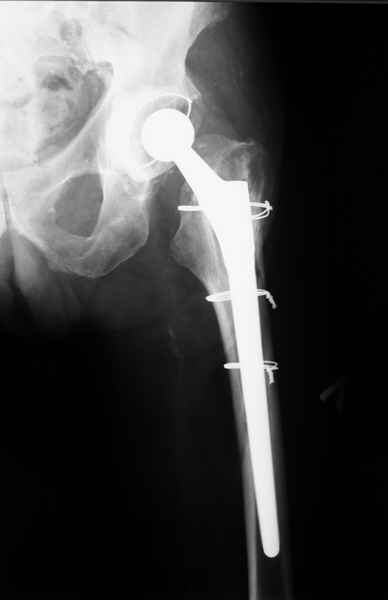

Произведено закрытое удлинение ножки эндопротеза с помощью ретроградного интрамедуллярного стержня. Продолжительность операции 3 часа. Два из них закрытое восстановление длины бедра диистрактором

таз-бедро.

новые снимки

Пациента удалось осмотреть недавно. Достигнутый результат сохраняется. Перелом бедра сросся. Конечность опорная и безболезненная, ходит без трости. Ножка, похоже, реинтегрировалась, как и надеялись. Снимки и фото в приложении. Комментарии приветствуются.

Надо ли что-то делать дальше, как полагаете? Убрать винты? Убрать "удлинитель ножки"? Или оставить все, как есть? Спасибо заранее.